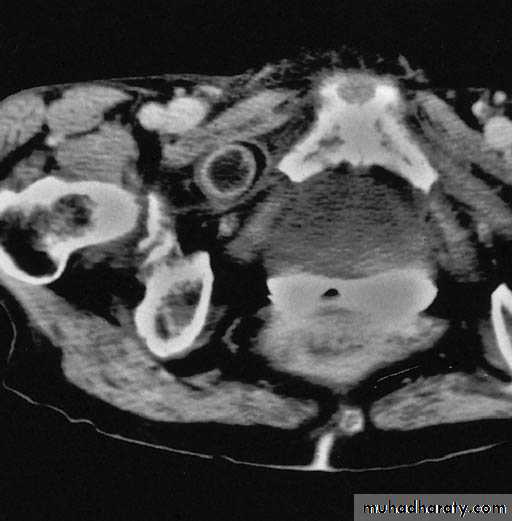

MRI

CT

Obturator HerniaOperative Approach

• REPAIR• Simple closure of the hernial defect with one or more interrupted sutures

• Plugging the canal with cartilage, free omentum ,obturator fascia, polypropylene mesh, teflonpatch, or bladder wall.

• Recurrence – 10% for simple closure

Intraoperative image showing left sided obturator hernia within white outline and incidental femoral hernia at 11’o clock position.

Noel P. Lynch et al. J. surg. case rep. 2013;2013:rjt050